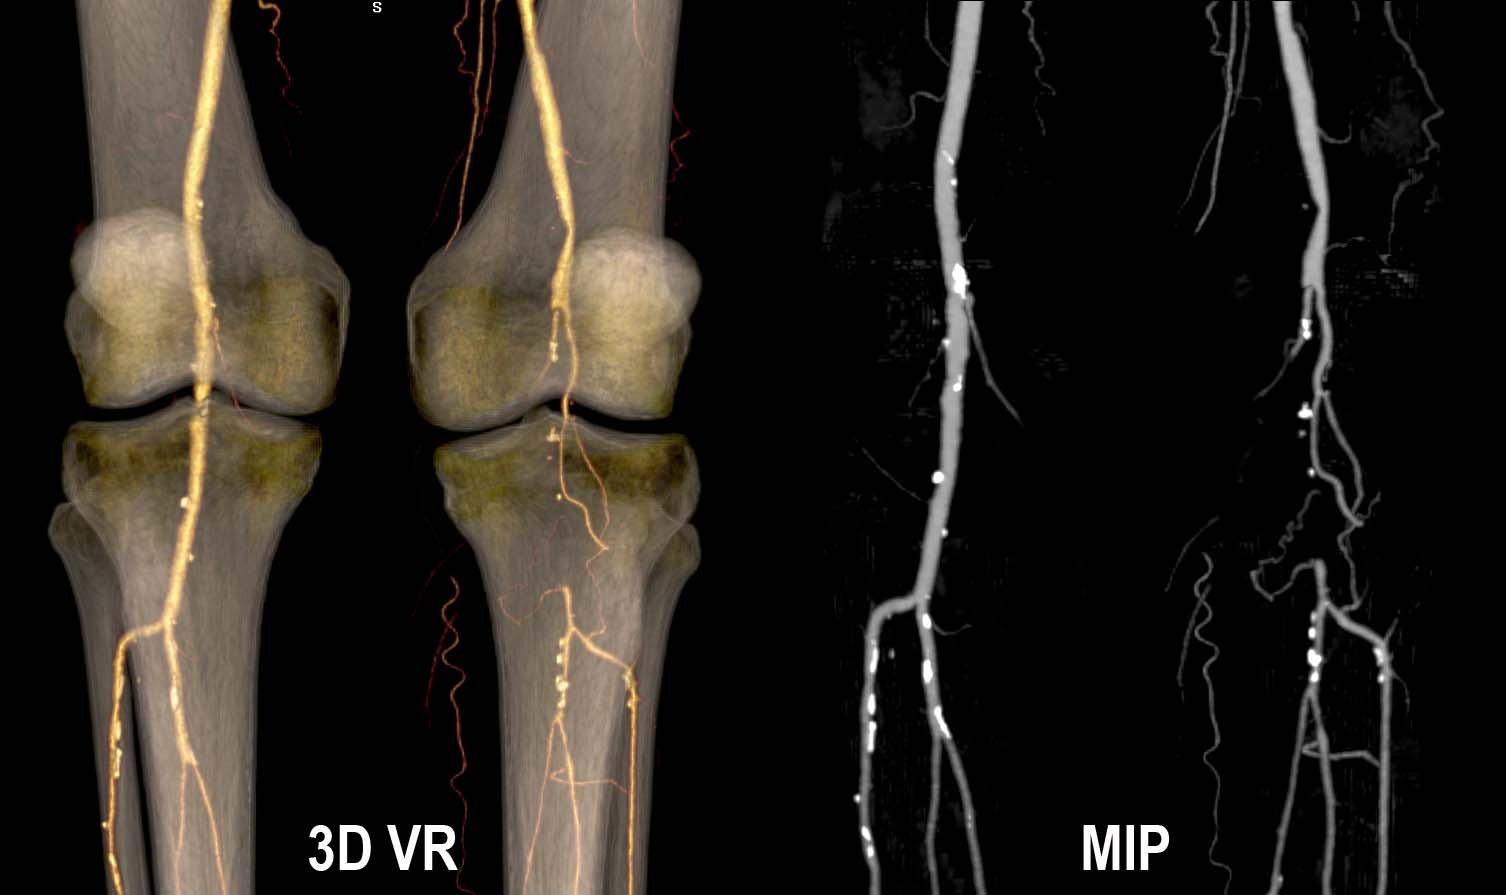

1. Al paciente se le realizó angioTC de extremidades inferiores. ¿Cuál es el hallazgo más relevante que se observa en las reconstrucciones 3DVR y MIP de dicha exploración?

- A. Obstrucción de arteria poplítea izquierda.

- B. Estenosis de arteria poplítea izquierda.

- C. Aneurisma de arteria poplítea izquierda.

- D. Obstrucción de arteria femoral superficial izquierda.

- E. Disección de arteria poplítea izquierda.